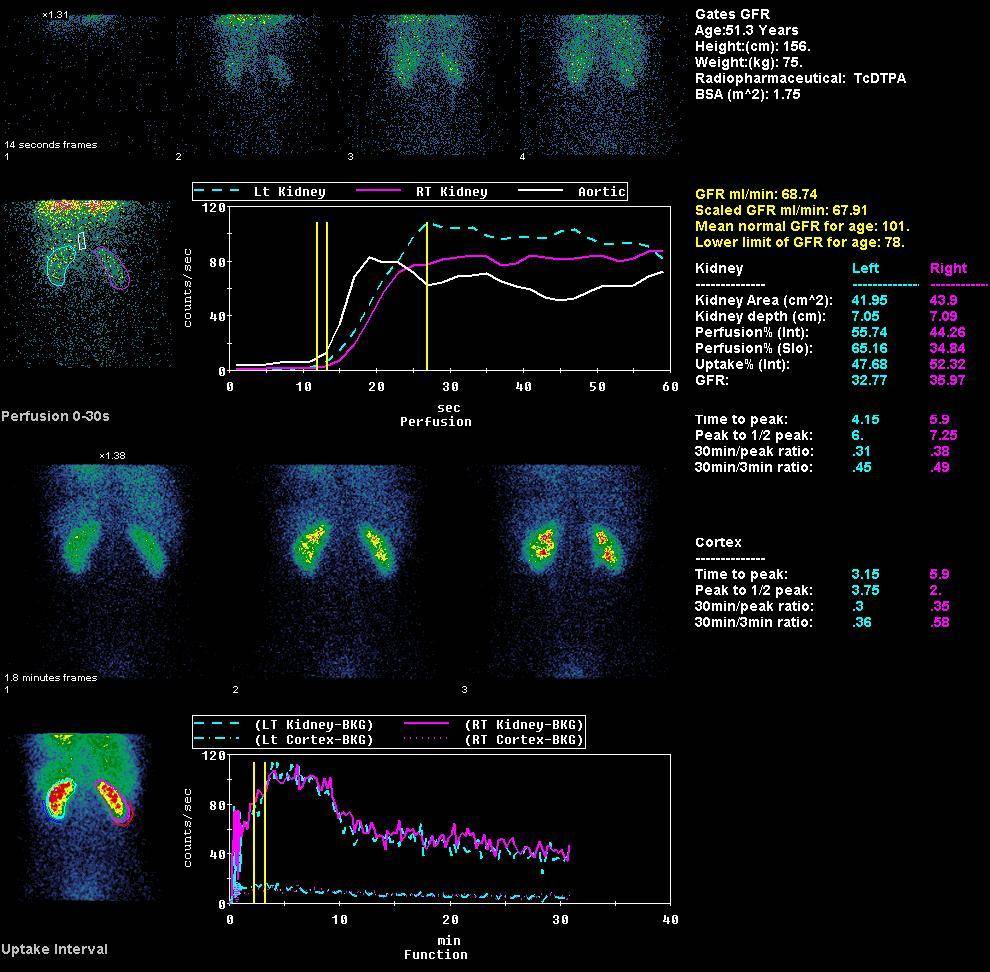

Динамическая нефросцинтиграфия:

image

• Динамическая нефросцинтиграфия Пентатех, Тс99м (99мТс-ДТПА): препарат быстро выводится из кровотока путем клубочковой фильтрации и попадает в канальцевую систему почки, что позволяет эффективно оценить уродинамику у каждого конкретного пациента. В норме через 2ч после введения из организма выводится более 90% препарата, что обуславливает очень низкую лучевую нагрузку.

• Количественная оценка скорости клубочковой фильтрации раздельно для каждой почки (более чувствительная методика, чем применяемые расчётные формулы, основанные на уровне креатинина)

• Раздельная оценка фильтрационной и экскреционной (выделительной) функции почек

• Оценка вклада каждой почки в суммарную функциональную активность